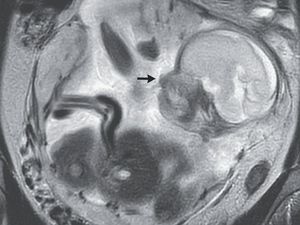

Sering Nyeri Perut Bagian Kiri Bawah-Susah Napas, Apa Penyebabnya Dok?

Nyeri perut bisa disebabkan banyak hal, tergantung bagian mana yang terasa sakit. Jika bagian kiri bawah yang sakit hingga susah napas, apa penyebabnya Dok?